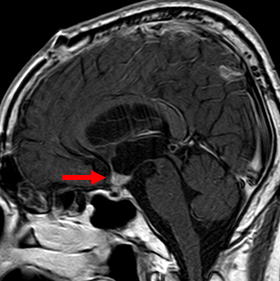

この患者さんは、開頭にて下垂体柄から視床下部の一部を除き、腫瘍の亜全摘を行いました。(図2-a,b,c)術後、水頭症も改善しており、術後3ヶ月後に残存腫瘍にガンマナイフ照射を行い、現在、8年経過しておりますが再発なく経過しております。

図2-a 術後5ヶ月後です。矢印の腫瘍は摘出されています。 |

図2-b 矢印の様に下垂体柄周囲に腫瘍像が一部残っていますがその他の腫瘤は摘出されています.脳室は大きいですが、術後見当識障害は改善し、正常に戻り、水頭症の症状を認めていないので経過観察としております。 |